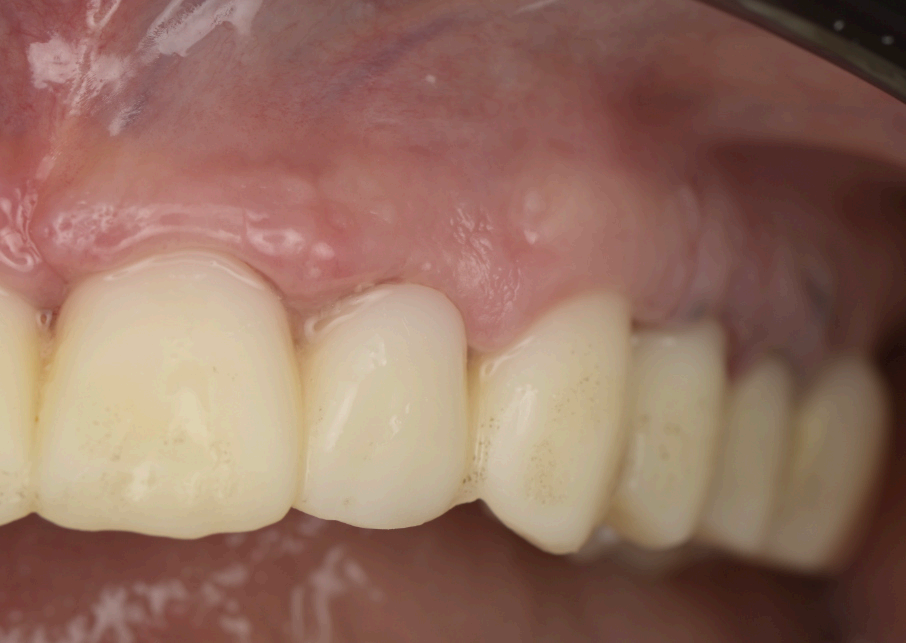

Group 6: Gingival Healing • Fig. 6.1, 6.2: Mature scalloped gingival profle at 2 months. • Fig. 6.3–6.6: Clinical views of the gingiva with the refned provisional in place.

At three months post-surgery, the soft tissues exhibited a mature, festooned contour that enhanced the aesthetic integration of the prosthesis (Fig. 6.1, 6.2). The refned provisional had successfully guided this outcome, with the gingival margins aligning seamlessly with the prosthetic teeth (Fig. 6.3–6.6). The fnal zirconia-iBar prosthesis demonstrated excellent stability, with no signs of mechanical complications or peri-implant infammation (Fig. 7.1). Aesthetically, the restoration fulflled the patient’s expectations, achieving a natural smile with balanced proportions and a lifelike gingival appearance. Functionally, the patient reported full satisfaction with mastication and speech, indicating a successful rehabilitation.

The fnal prosthesis was designed as a hybrid structure, combining a translucent zirconia framework with a metallic iBar for strength and durability (Fig. 7.2, 7.3). The iBar was modeled in Blender4Dental, optimizing its geometry to distribute occlusal forces across the six implants (Fig. 7.4). The zirconia component was milled to achieve a natural translucency, mimicking the optical properties of natural teeth. After fabrication, the prosthesis was inserted, secured to the MUAs via screw retention, and adjusted to ensure proper occlusion and patient comfort (Fig. 7.1). The fnal design adhered to FP1 principles, replacing only the dental crowns while harmonizing with the scalloped gingival profle established during healing.